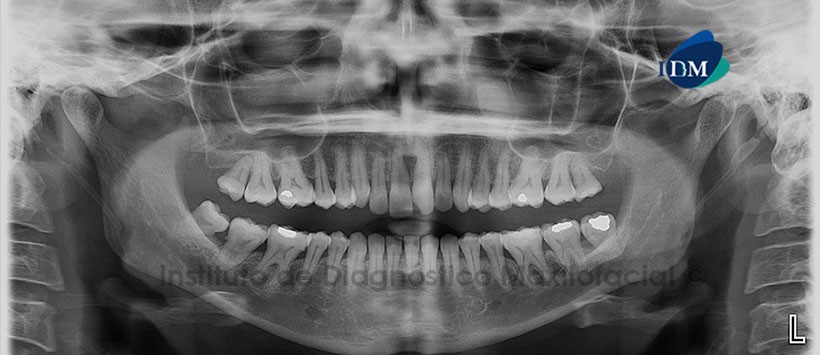

En la radiografía panorámica (Figura 1) se aprecia fractura coronaria inciso-mesial en pieza 2.1 y ensanchamiento del espacio periodontal de piezas 11 y 21.